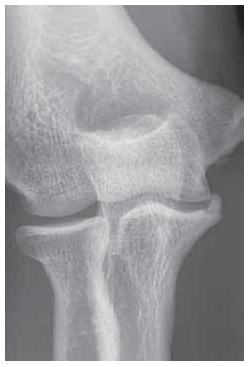

Radiography and computed tomography were performed (Figures 1–3). An aseptic necrosis was detected in the region of the tubercle of the coronary process in the fragmentation stage.

Fig. 1. Radiograph of the left elbow joint. Fragmentation stage of the region of the coronoid process tubercle